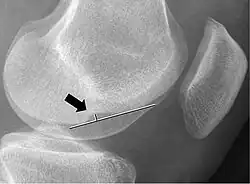

Measurement technique to determine the depth of the femoral notch on lateral x-rays

In radiology, the deep lateral femoral notch sign is a finding on a lateral radiograph that is considered an indirect sign of a torn anterior cruciate ligament (ACL).[1][2] It is an abnormal deepening of the lateral condylopatellar sulcus from an osteochondral impaction fracture.[1][3] A depth greater than 1.5 mm (0.059 in) is a reliable sign of a torn ACL.[1]